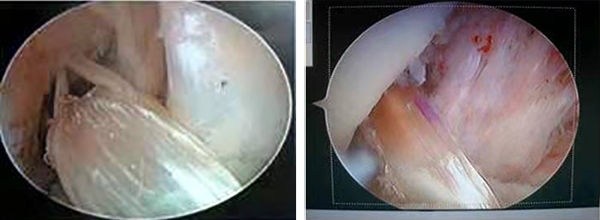

1、关节镜下前、后交叉韧带重建术

1999年购置三门峡地区首台关节镜,率先开展了关节镜下微创手术并在同年开展了膝关节镜下前交叉韧带重建术,是豫西地区最早且当时唯一能开展镜下病检、滑膜及半月板切除、交叉韧带重建的科室,目前已达省级医院水平。完成的“关节镜下应用四股腘绳肌腱保留残端重建前交叉韧带” 、“关节镜下联合修补技术治疗半月板损伤”经三门峡市科技局组织专家鉴定,一致认为:此项技术达到了省内先进水平,填补了地区技术空白,,分别荣获2013年河南省卫生厅科技进步三等奖、三门峡市人民政府科技进步三等奖、2014年三门峡市人民政府科技进步三等奖。